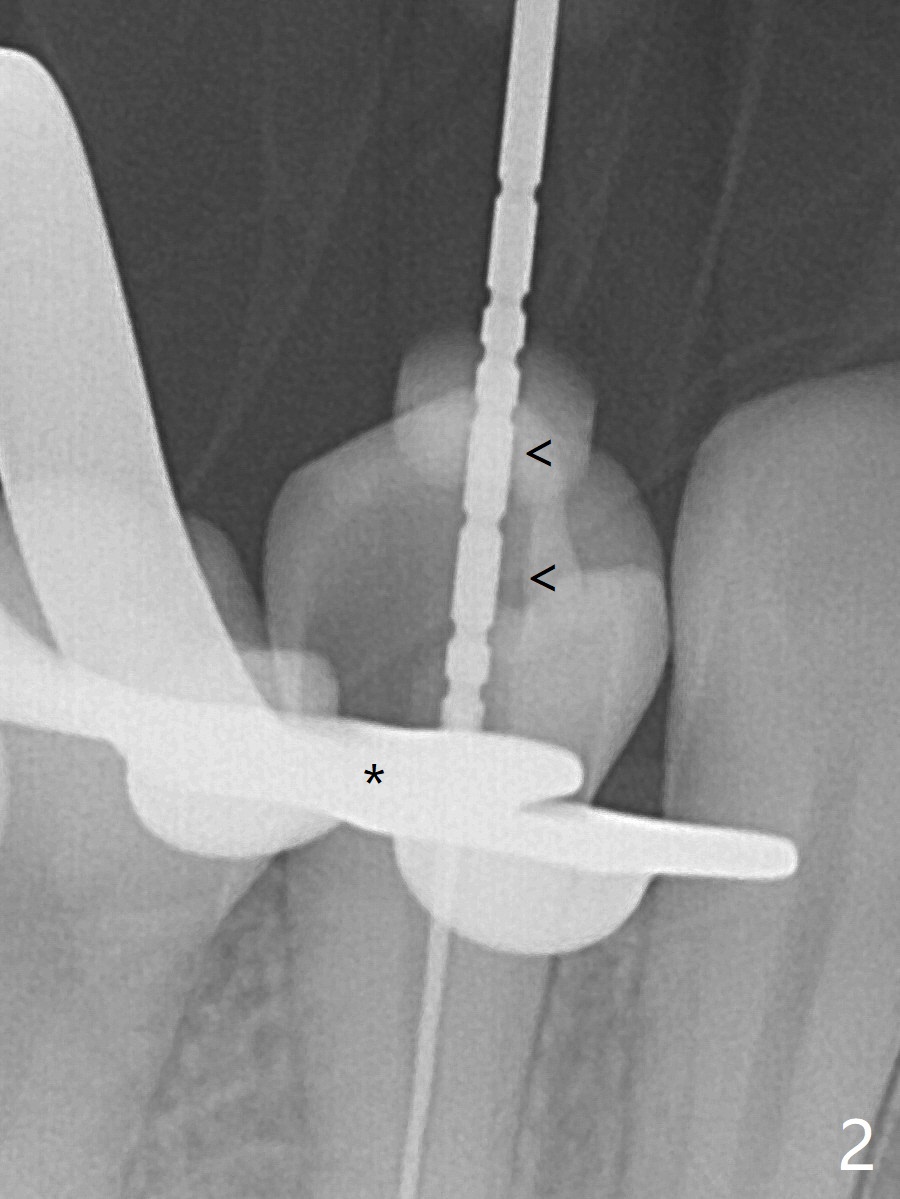

25岁硕士生,女,要求右下4补牙(图一:第一前磨牙),经过解释,欣然接受根管治疗。后者要领基本四条:无菌,根管笔直通畅,使用根尖定位仪和旋转式锥形扩大针和锥形牙胶尖。为了无菌,局麻后常规使用橡皮障(图二 *)。防止断针,尤其是旋转式锥形扩大针,根管治疗开口尽量大(图二箭头),保持扩大针笔直。开始根尖定位仪有点毛病,使用15号锉测定根管长度,不小心超越根尖大约3毫米(图三)。后来倒退4毫米,并得到根尖定位仪证实,主牙胶尖(30/.06)好像长度合适(图四),反复冲洗,最后再插入一个细牙胶尖一次性完成根管治疗和补牙(图五,六)。